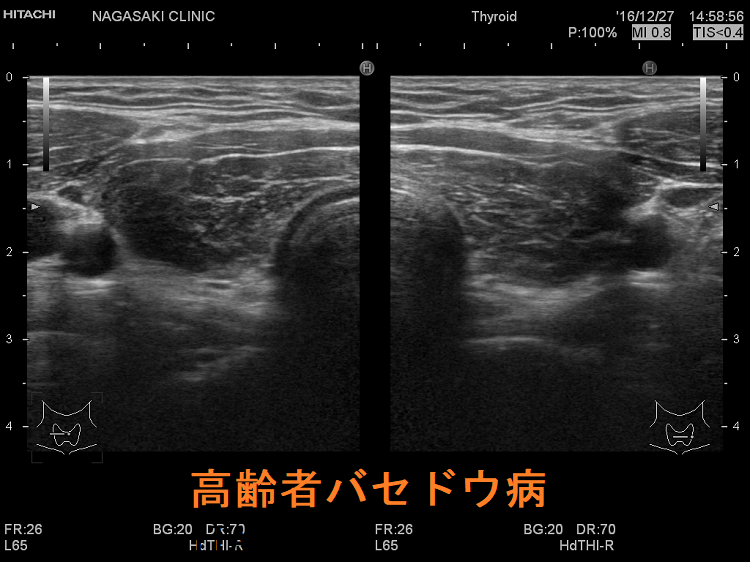

高齢者甲状腺機能亢進症/バセドウ病は、若年性バセドウ病、中年性バセドウ病と異なる症状を呈します[Arch Intern Med. 1988 Mar;148(3):626-31.]。甲状腺が腫れにくい(甲状腺が小さい)ため、甲状腺の病気が見逃され易い[バセドウ抗体(TRAb)に対する反応性低下のため]。